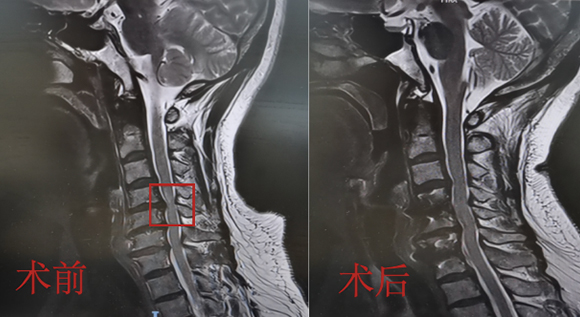

脊柱脊髓神经微创中心以微创技术为引领,以功能恢复为目标,主要治疗脊柱外伤、肿瘤、退行性病变、脊柱畸形等疾病。团队利用神经外科显微技术,结合神经内镜微创技术,对脊柱间盘变性疾病、颈腰椎管狭窄、颈腰椎间孔狭窄、颈腰椎间盘突出、颈腰椎体不稳、脊柱骨折、寰枢椎脱位、脊柱肿瘤、椎管内肿瘤、脊髓损伤、脊髓空洞、脊髓栓系等疾病进行高效、特色手术治疗,如颅颈交界区畸形寰枕减压内固定术、脊柱肿瘤全脊椎切除内固定术、微创椎管内肿瘤切除术、微创脊柱旁肿瘤切除术、寰枢椎脱位椎间融合内固定术、脊柱骨折微创经皮椎弓根钉内固定术、经椎间孔椎间融合内固定术(MIS—TLIF)等,最大程度降低脊柱脊髓手术创伤,具有创伤小、输血少、恢复快、口碑好,出院早等优势。